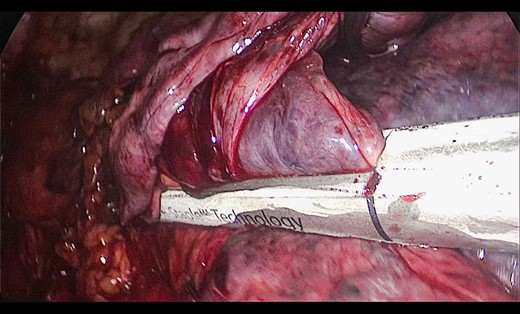

A 73-year-old male patient with a clinical history of COPD, lung emphysema and a 30-year smoking history was admitted to the ED due to a 24-h clinical picture of dyspnea immediately following a sudden bout of dry coughing. Physical examination showed a dyspneic patient, tachypnea of 25 rpm, heart rate of 85 bpm and blood Pressure of 135/75 mmHg along with central cyanosis. Chest exam showed a hyper-resonant right hemithorax along with reduced breath sounds. Initial chest X-ray revealed a large right-sided pneumothorax (Fig. 1). A right chest tube was placed in the ED. Emergency echocardiogram had no significant findings and spirometry showed suspected patterns of obstruction. Following patient stabilization, a high-resolution chest computed tomography (HRCT) was performed revealing extensive pan lobar emphysema throughout both lungs, para septal emphysema in both the anterior upper lobes and herniation of a left lung bullae through the anterior mediastinal pleura along with a right-sided pneumothorax with the chest tube in place with persistent air space (Fig. 2). The patient was taken to surgery where a right video-assisted thoracoscopic (VATS) approach showed severe lung emphysema and a contralateral herniated left lung bulla through the mediastinal pleura anterior to the pericardium (Fig. 3). Right pleurodesis was performed using Talc and a left posterior thoracoscopy showed a severe emphysematous left lung with a lingular herniated bulla to the right hemithorax through an anterior mediastinal pleural defect along with pleural adhesions (Figs 4 and 5). Thoracoscopic hernia reduction was performed along with bullectomy using 60 mm mechanical sutures (Fig. 6). Chest tubes were removed on POD 3 (right) and POD 4 (left). The patient had significant respiratory improvement and was discharged on POD 5.

Thoracoscopic view from left side of thoracoscopic bullectomy.